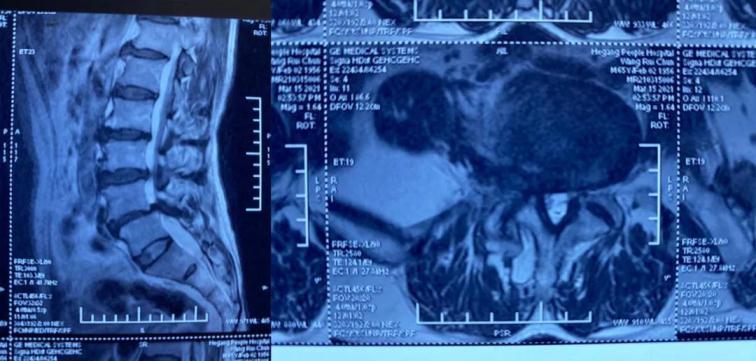

術(shù)前MRI